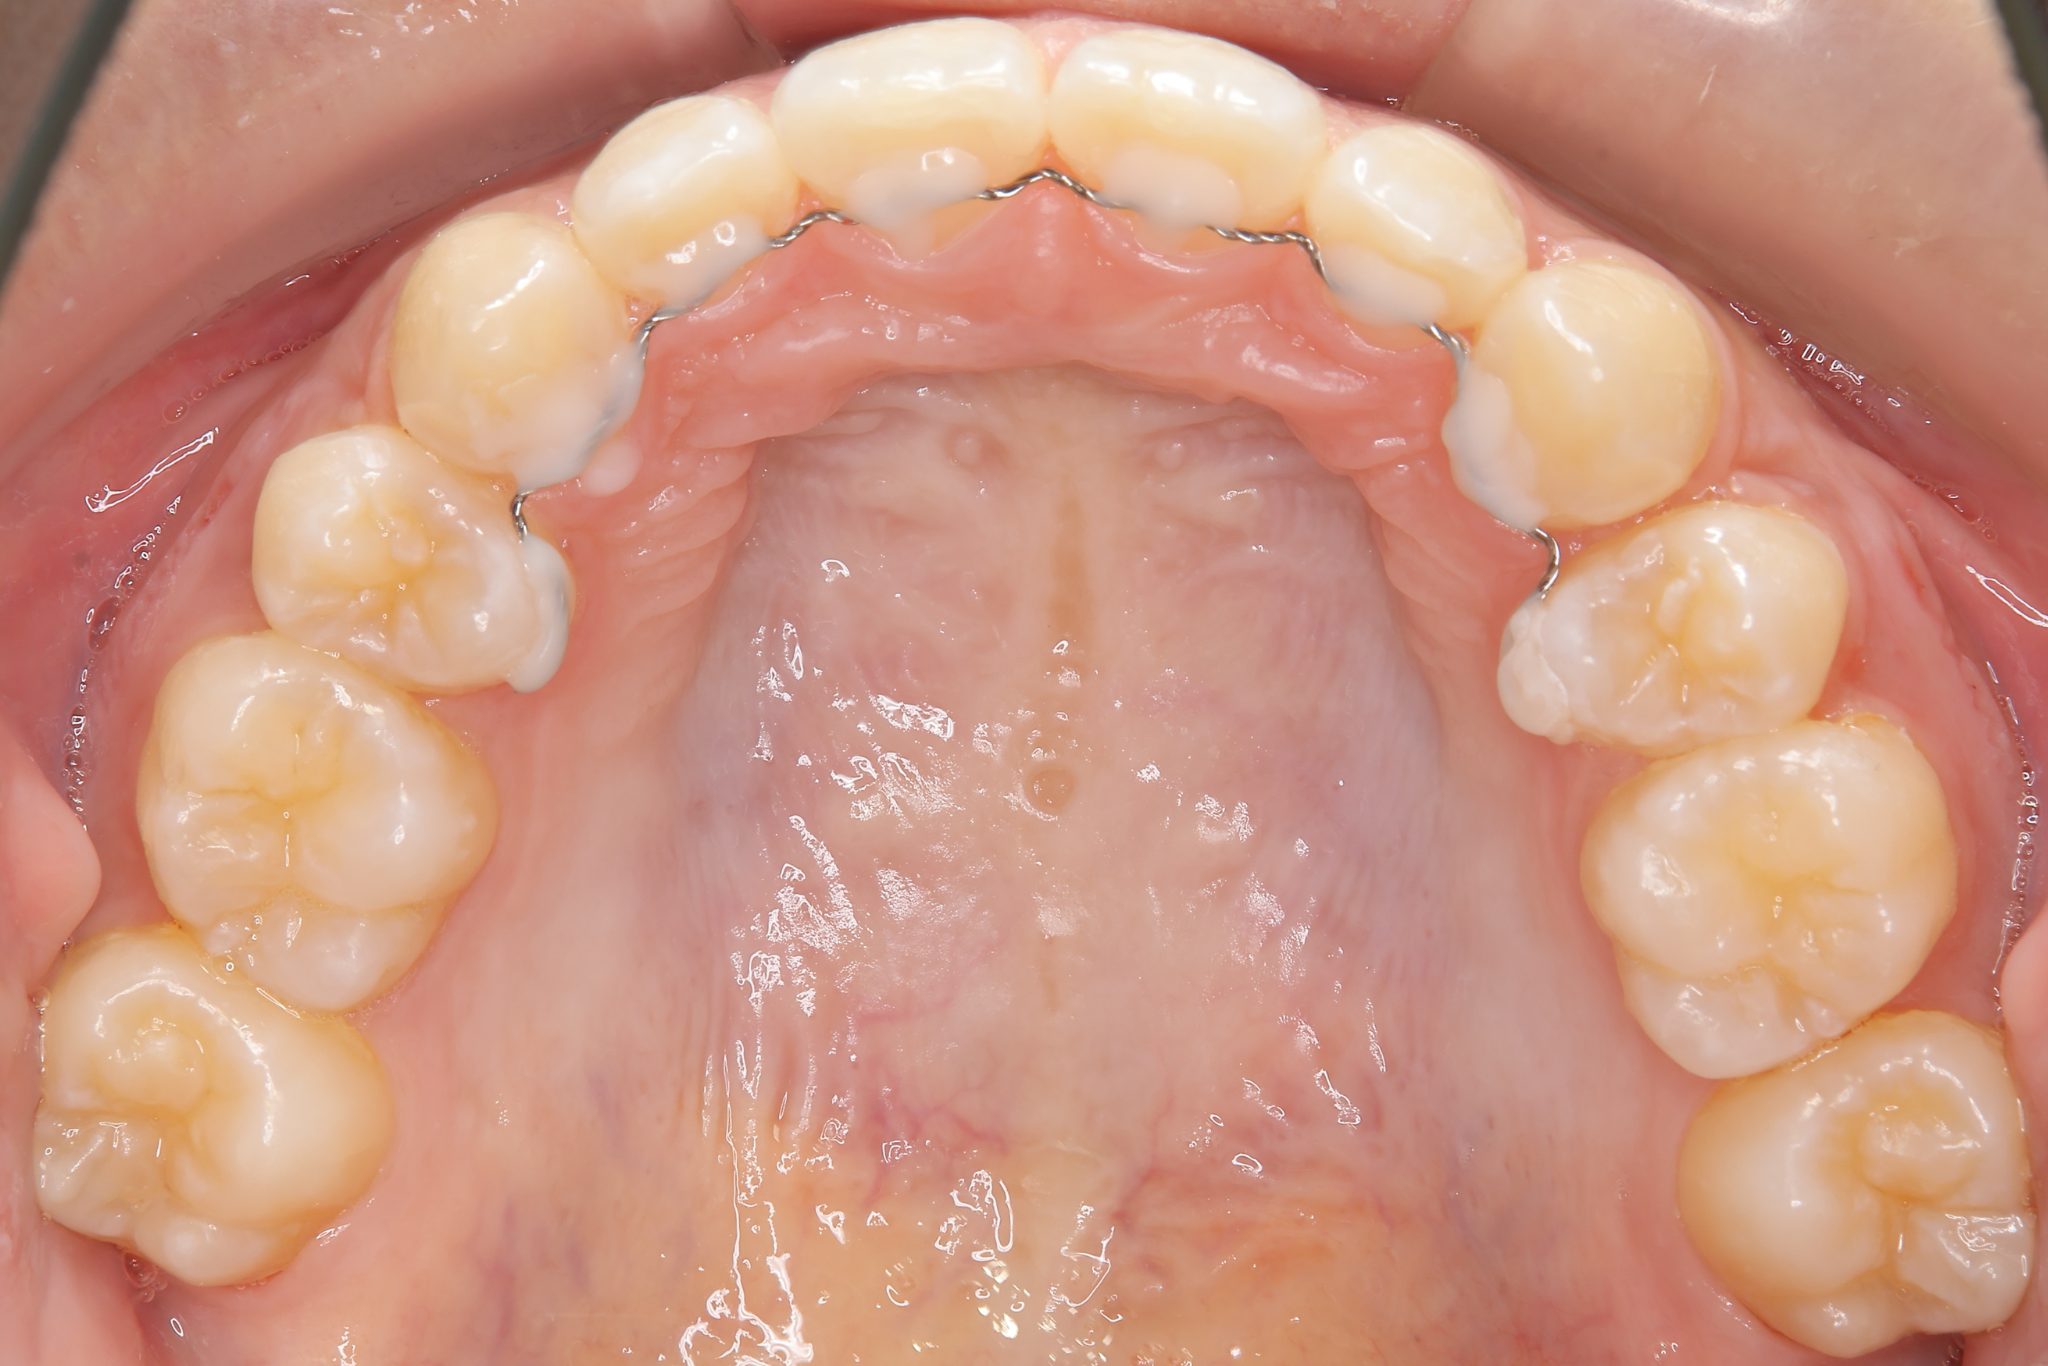

ビフォー

全顎ワイヤー矯正 症例_418